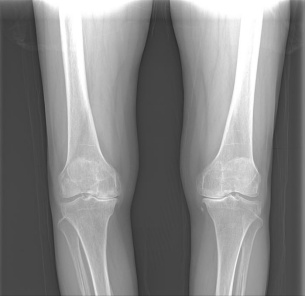

②关节畸形:膝关节因骨赘形成或滑膜炎症积液也可造成关节肿大,膝关节内翻或外翻畸形(即O型腿或X型腿)。

① X线:为膝骨关节炎明确临床诊断的“金标准”,是首选的影像学检查。X线片上的三大典型表现为受累关节非对称性关节间隙变窄、软骨下骨硬化和(或)囊性变、关节边缘骨赘形成。部分患者可有不同程度的关节肿胀,关节内可见游离体,甚至关节变形。

③ 保膝:是一种旨在通过纠正局部骨骼形状来改变整个下肢力线的手术。年纪很轻,膝关节磨损比较局限,但力线已经发生了明显改变,医生可能会建议您先做“截骨保膝”手术。截骨术不是永久性的,以后可能需要进一步手术。